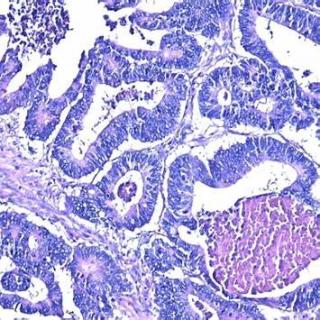

Высокодифференцированная аденокарцинома представляет собой злокачественную опухоль железистого происхождения, клетки которой сохраняют значительную часть признаков нормальной ткани, поэтому опухоль часто растёт медленнее и даёт меньше ранних метастазов по сравнению с низкодифференцированными вариантами